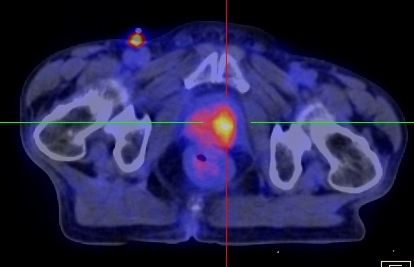

Hình 2 ghi lại kết quả chụp PET/CT của bệnh nhân Trịnh Th. T. L., nữ, 66 tuổi, gần đây thấy xuất hiện ù tai trái, hạch cổ trái. Sinh thiết hạch cổ trái là ung thư biểu mô di căn hạch chưa rõ nguyên phát. Bệnh nhân được chỉ định chụp PET/CT để tìm ổ ung thư nguyên phát.

Hình 2: Hình PET toàn thân và hình PET/CT thấy tổn thương ở vùng vòm (mũi tên đỏ) và hạch góc hàm (mũi tên xanh) tăng hấp thu FDG. Hình ảnh hướng đến ung thư vòm di căn hạch góc hàm trái. Bệnh nhân đi nội soi và bấm sinh thiết vùng vòm trái cho kết quả ung thư biểu mô tế bào vẩy.